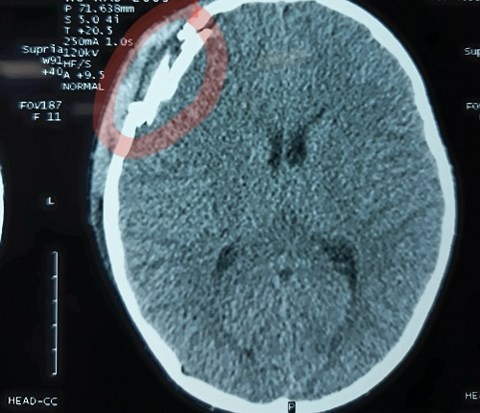

Hình ảnh chụp CT Scanner cho thấy sọ não cháu Điệp bị tổn thương nặng.

Qua hình ảnh chụp phim CT Scanner cho thấy nạn nhân bị chấn thương sọ não, vỡ xương sọ vùng trán và tụ máu ngoài màng cứng. Em Hồ Đ. được các bác sĩ phẫu thuật chữa trị, hiện đã qua cơn nguy hiểm, sức khỏe dần ổn định.